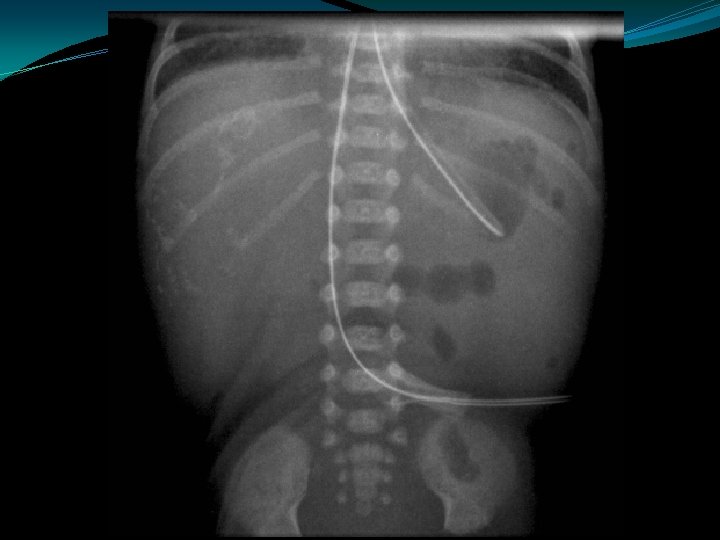

Meconium Plug Syndrome �Diagnosis of exclusion �Probably same as "small left colon" syndrome �Transient disorder due to functional immaturity of colon �Common in IDM, premies, PIH, Mg Rx �Infants with CF may present with mec plugs, although mec ileus most common � 10 -30% may have Hirschsprungs also

Meconium Plug Syndrome �Present within the first 24 to 36 hours of age: �Abdominal distention �Vomiting (bilious) �Failure to pass meconium �Plain films show distal intestinal obstruction �Contrast enema usually shows: �distention of the right and transverse colon �transition near the splenic flexure to a narrow descending colon and rectosigmoid region �Meconium within the colon �Main differential diagnosis is Hirschsprung's disease: �In Hirschsprung's disease, aganglionic colon is usually normal caliber �In Meconium Plug Syndrome, colon is usually small